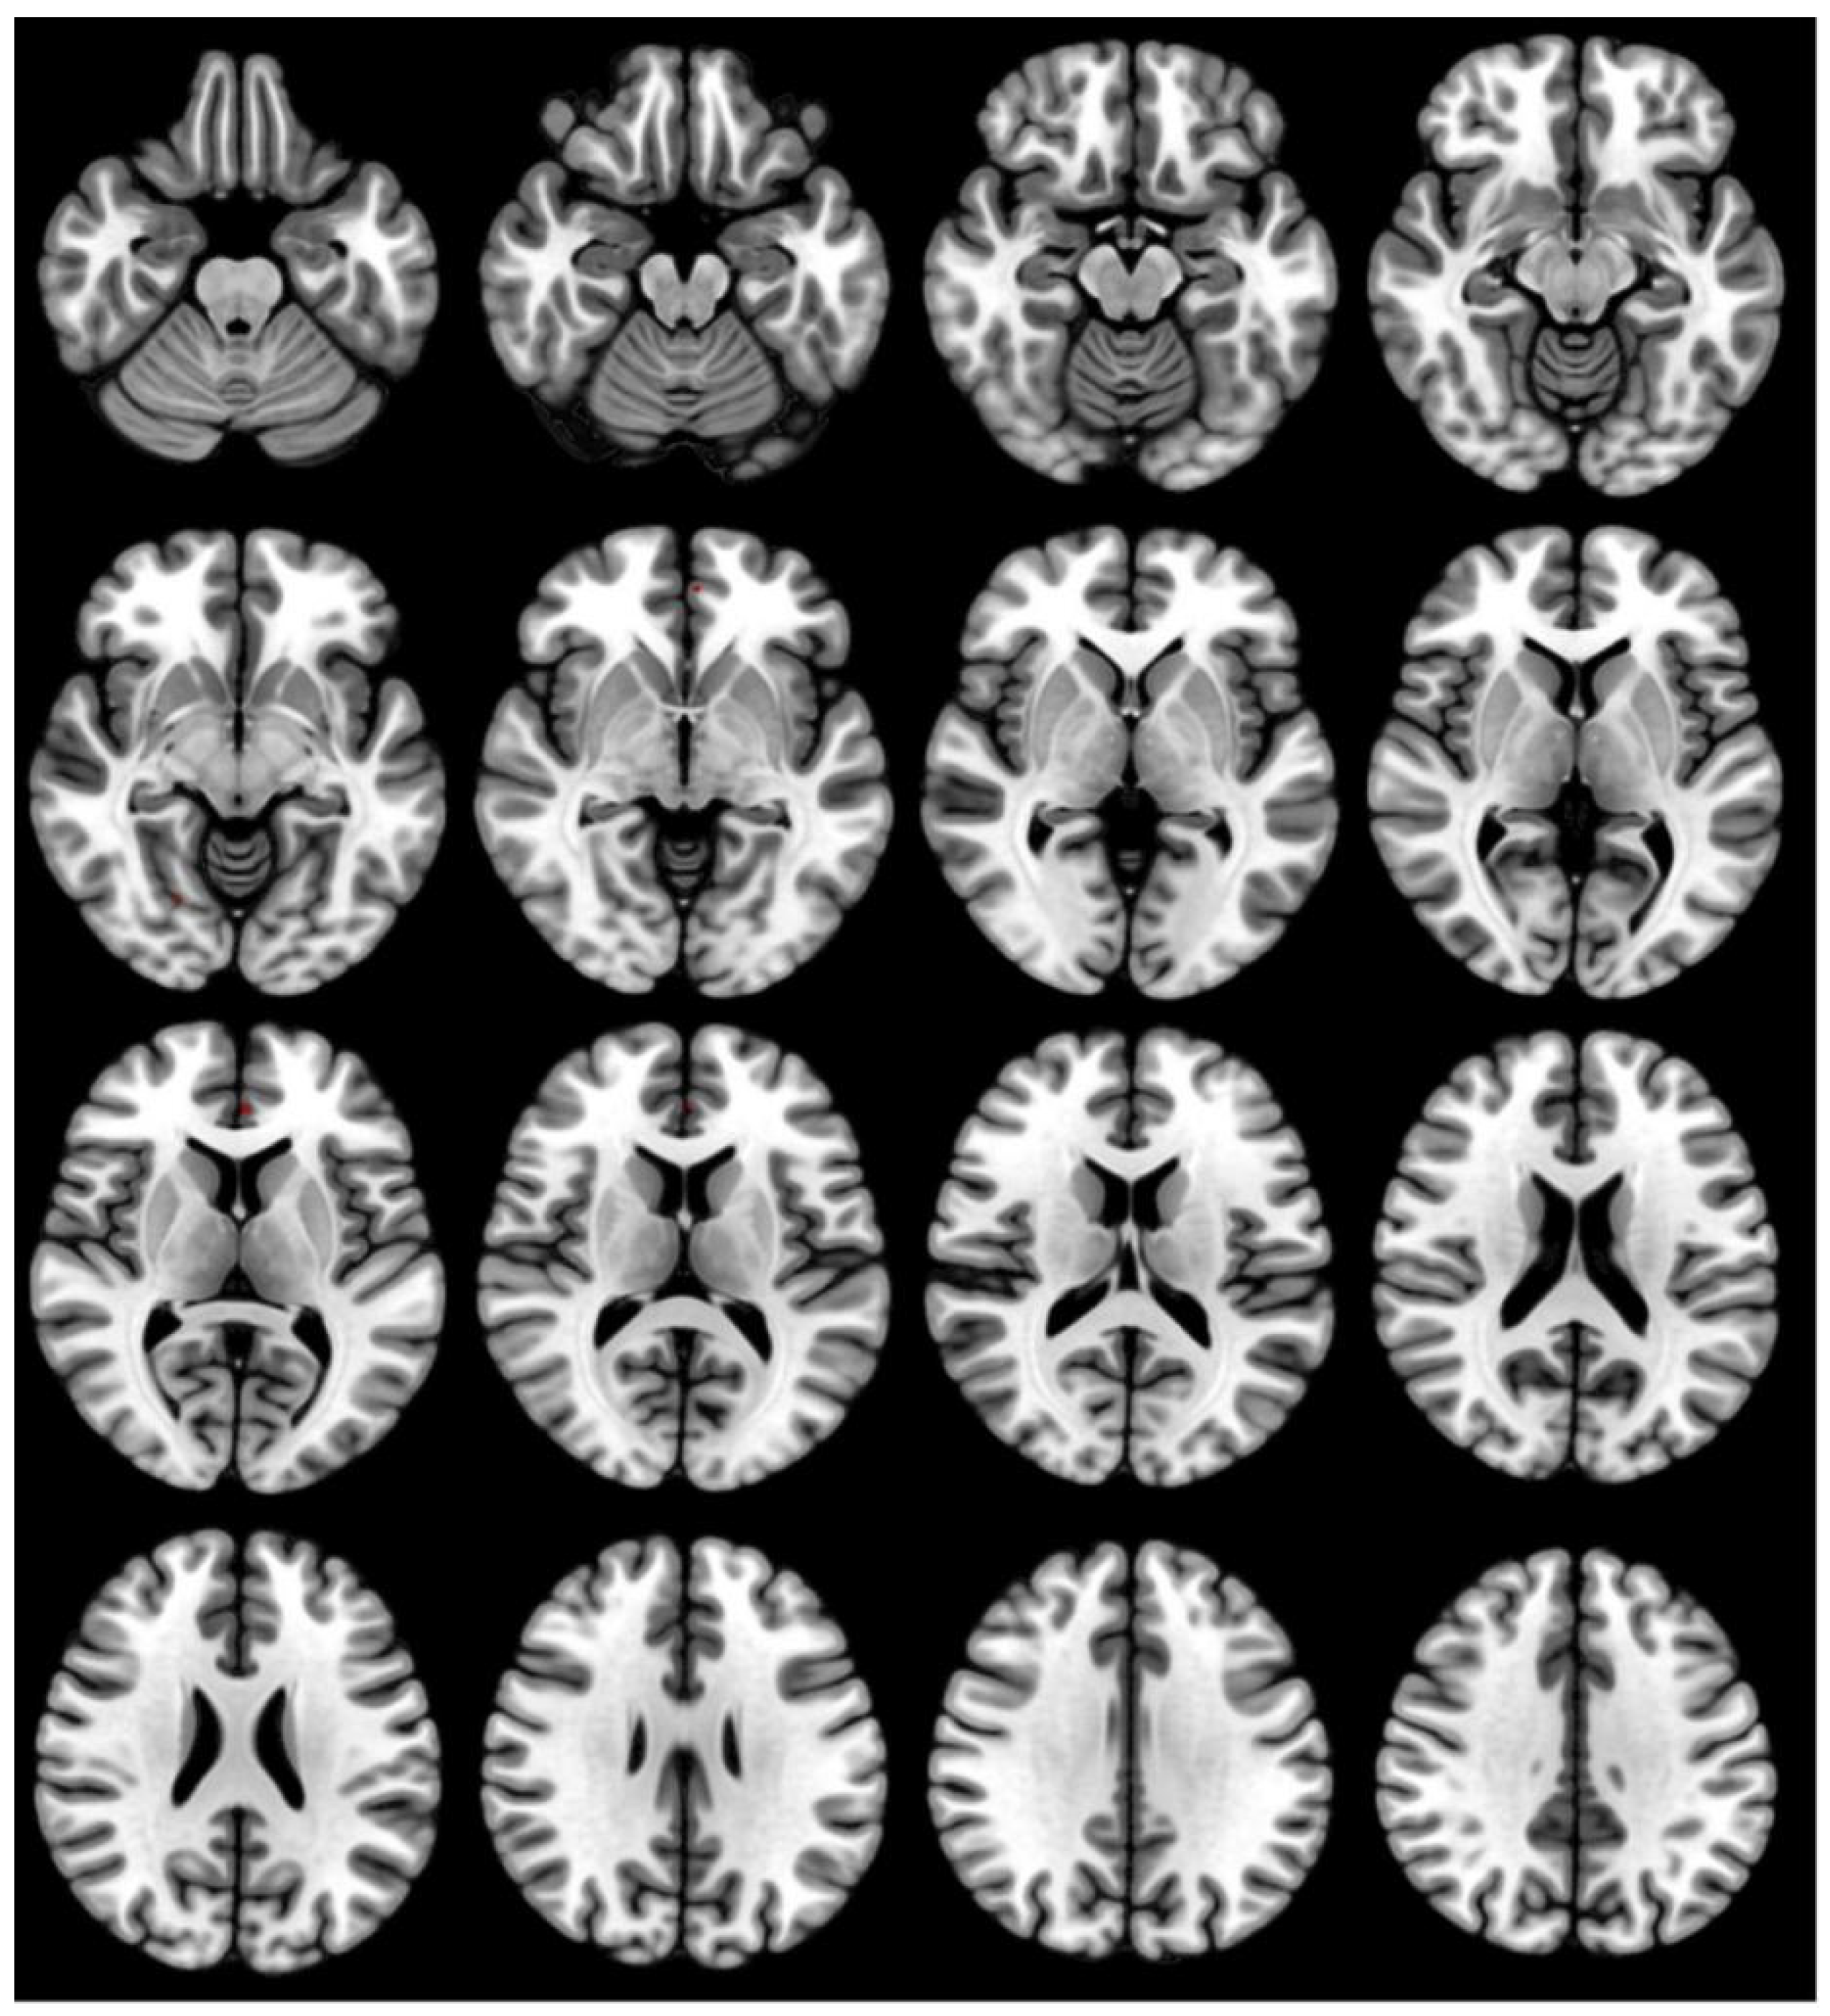

3.3. GMV Differences before and after Acute SD